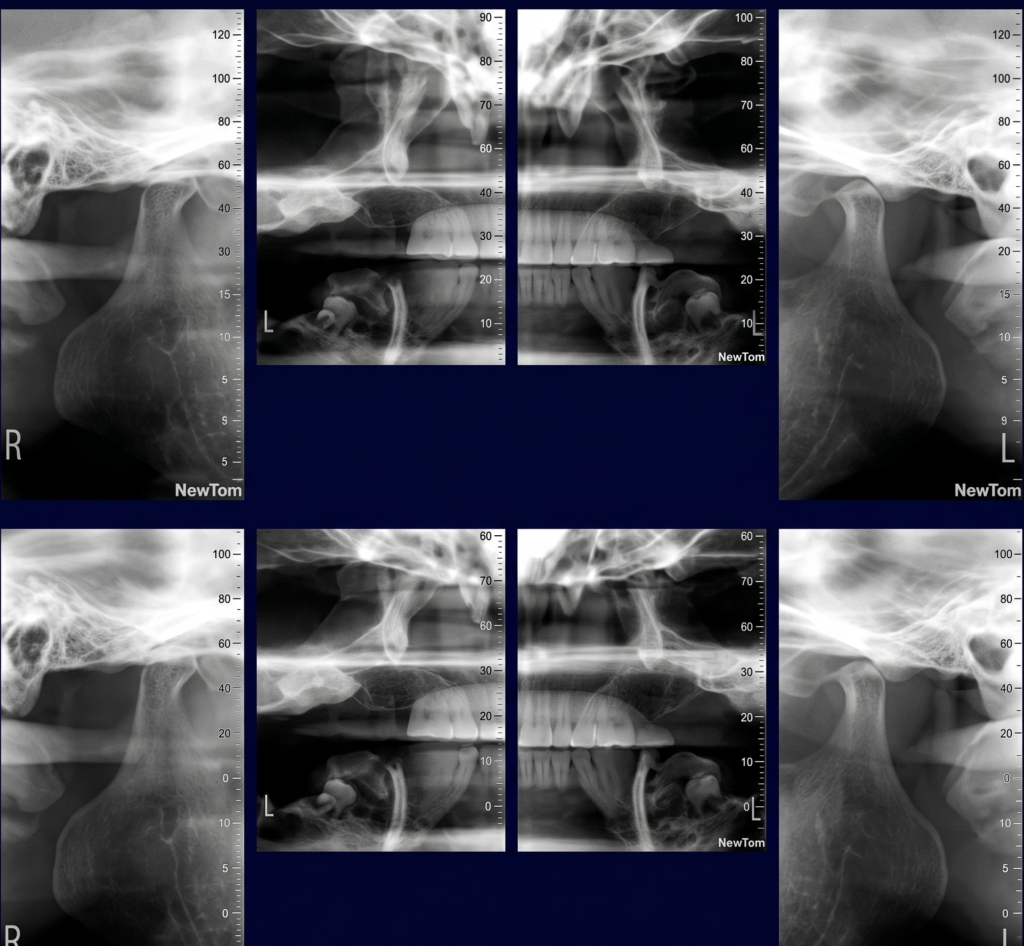

He is certified in Cone Beam Computed Tomography (CBCT) and has extensive experience in advanced radiological diagnosis. Dr. Singh is associated with several reputed centers across India as a consultant radiologist for CBCT reporting. His expertise includes implant planning, impacted teeth localization, oral and maxillofacial pathology interpretation, TMJ assessment, maxillary sinus evaluation, and airway analysis.

Bilateral TMJ (open and close mouth) – 3D Scan 3500/-

Unilateral TMJ (open and close mouth) 1800/-

Bilateral TMJ (open and close mouth) – 2D Radiograph 1000/-